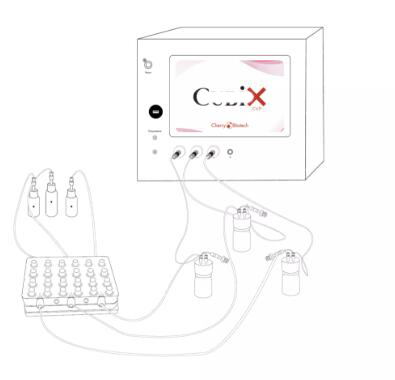

即插即用系统,该系统利用了器官芯片技术和人工智能分析的优势。 该装置 允许在受控微环境中执行所有体外实验,自动采集光学、生化和电生理参数。

主要特点

1、无需培养箱

4、与实时成像宛兼容的微环境控制器

5、具有可扩展性和可定制性,允许您使用定制芯片、多孔芯片、商用微流控芯片等,帮助您获得更好、更长久的生物培养

6、它可以长期培养人体组织和活检、3D 细胞模型或器官芯片模型。